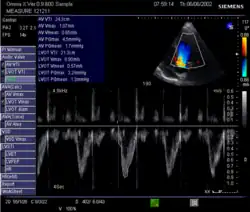

Umfahrung des PW-Doppler-Signals im LVOT: Velocity Time Integral (VTI)

1. In der Echokardiografie: Einfach ist es aus dem Schlagvolumen und der Herzfrequenz berechenbar: HMV = Herzfrequenz × Schlagvolumen. Das Schlagvolumen und die Herzfrequenz können aus der Echokardiografie abgeschätzt werden. Der Durchmesser des linksventrikulären Ausflusstraktes (LVOT) wird im 2D-Bild gemessen und daraus wird mit Hilfe der Kreisformel A = πr² die Querschnittsfläche berechnet. Diese Querschnittsfläche wird dann mit der Umfahrung der PW-Doppler-Kurve im LVOT, dem Velocity Time Integral (VTI), sowie mit der Herzfrequenz (HF) multipliziert. HMV = π × LVOT²/4 × VTI × HF.[20]